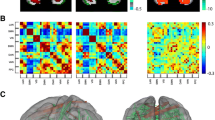

Using graph theory analysis over the entire brain, we also found some significant differences between preterm and full-term infants. Assortativity was significantly decreased in preterm infants (p < 0.05) across the full range of cost function values tested (Fig. 4a). Differences in small-worldness (\(\sigma>1\)) were not significant over a range of cost threshold (0.06–0.3), but at the cost level of 0.08–0.11, preterm infants showed higher small-worldness (p < 0.05) (Fig. 4b). Modularity (Q) was not significantly different between preterm and full term infants (Fig. 4c) over the entire range of cost levels we tested of 0.06–0.3. Figure 4d shows that preterm infants exhibit characteristic rich-club organization \(({\emptyset _{{\text{norm}}}}(k)>1)\) for the range of \(k=18~\) to \(k=30\) whereas full term infants exhibit characteristic rich-club organization \(({\emptyset _{{\text{norm}}}}(k)>1)\) for the range of \(k=15~\) to \(k=30\). Rich-club organization was significantly reduced in preterm infants for values of the Rich-club level > 15 (p < 0.05).

Comparison of global network measures between preterm and full term born infants plotted as a function of the cost threshold or rich club level (k) used to estimate the parameter: a small-worldness, b modularity, c rich-club coefficient, d assortativity. Asterisk indicates the difference is significant at p < 0.05 corrected for multiple comparisons using false discovery rate

Finally, we present region specific group differences in graph theory parameters in Fig. 5. By examining all 90 ROIs and all of the topological measures we calculated, we constructed the ball and stick representations shown in Fig. 5, of the specific areas where differences occur in the graphical measures between groups. These ROIs are also listed in Table 3. Differences are highlighted showing full-term infants with increased global efficiency and degree in frontal networks (SFGmed, SFGdor, MFG, and superior ORB) (Fig. 5a, b, red). Preterm infants exhibit increased global efficiency relative to full term in auditory, language networks (left Heschl’s gyrus-HES, superior temporal gyrus-STG) and primary motor networks (precentral gyrus-PreCG) and increased degree in auditory and language networks (HES, STG) (Fig. 5a, b, blue, respectively). Local efficiency and betweenness centrality were not significantly different between preterm and full term infants.

Group difference maps. Red indicates that the full-term group had greater global efficiency (a) or degree (b) compared with the preterm group while blue colors represent the converse with the preterm group exhibiting increases relative to the full-term babies. A threshold of p < 0.05 was used for all maps, with correction for multiple comparisons using false discovery rate

Using network measures from graph theory that reflect whole brain functional organization we demonstrated that preterm birth consistently alters network topology globally and that such effects are detectable by term-equivalent age. Comparing preterm and full-term infants at term-equivalent age, preterm infants showed reduced rich-club coefficient, assortativity and no significant difference in modularity (Fig. 4a, c, d). Rich-club coefficient identifies the tendency for high degree nodes to be more densely connected among themselves than with other nodes. This is directly consistent with a recent finding that rich-club organization and assortativity lowered in preterm infants but modularity is not significantly different between preterm and full term infants (Scheinost et al. 2015). Although a recent study (Scheinost et al. 2015) suggests reduced clustering coefficient in preterms, small-worldness was increased in preterm infants in our study, indicating increased clustering coefficient. Since network measures are very sensitive to cost threshold, we repeated the analysis across a range of cost thresholds that might effect results. Results remain reliable across a range of cost values. Furthermore, preterm infants had lower global efficiency and degree in frontal regions including premotor and cognitive function areas. However, connectivity within the auditory network appears to be enhanced in the preterm group. For this network, preterm infants exhibited increased global efficiency and degree; findings that are consistent with the seed-based analysis presented in Figs. 1, 2 and 3.